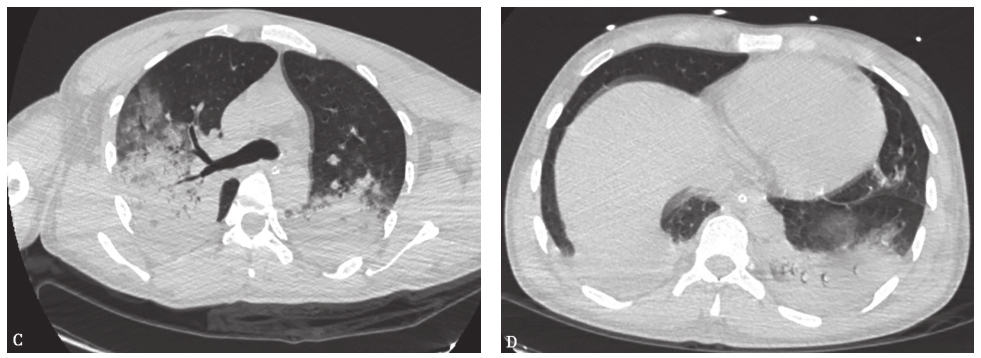

患者继续上述治疗,病情逐步好转,于发病后第7天脱机拔管,逐步降级调整抗感染药物后,康复出院。

出院前复查X线胸片见双肺原高密度阴影较发病时明显吸收(图3)。

图3 出院前(发病第13天)复查X线胸片